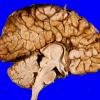

DEVELOPMENTAL MALFORMATIONS

Agenesis - Corpus Callosum

Agyria & Pachygyria

Anencephaly

Aqueductal Stenosis, Atresia & Septa

Atelencephaly-Aprosencephaly